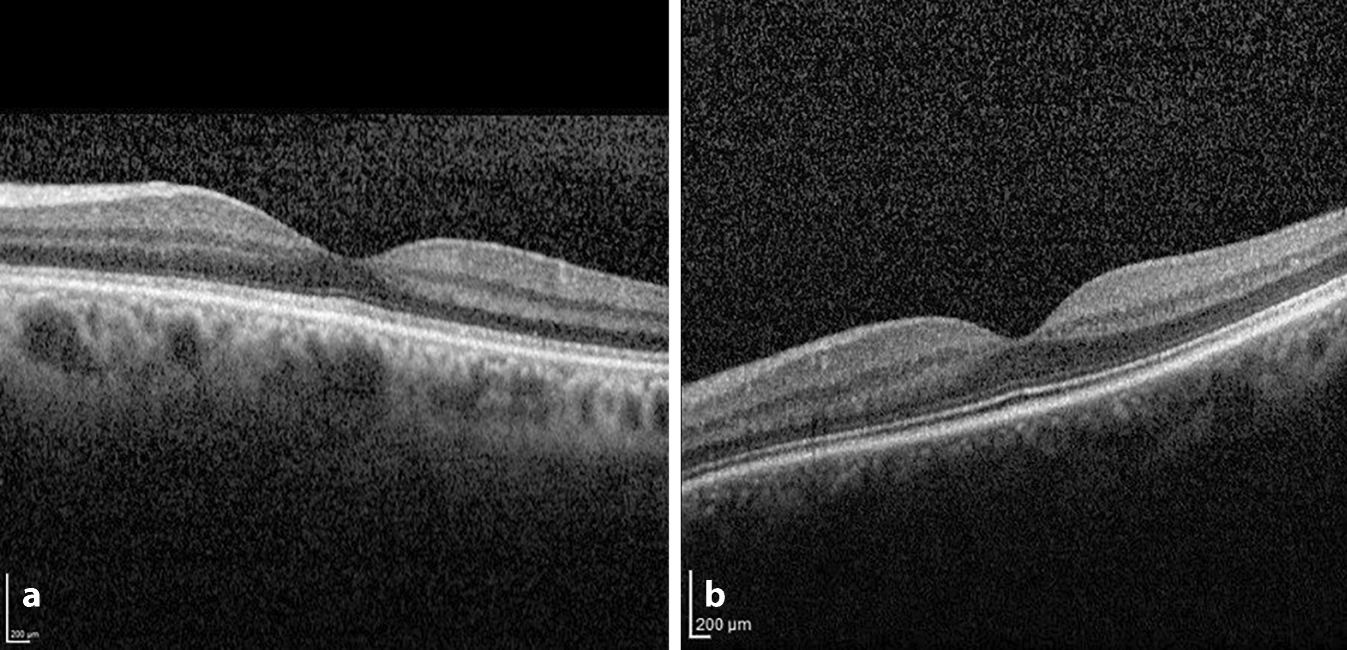

Der bestkorrigierte Fernvisus (BCVA) betrug an beiden Augen 0,4 dezimal. Der vordere Augenabschnitt (VAA) war bis auf eine konjunktivale Verdickung im Bereich der temporalen Konjunktiva und eine alte Hornhautnarbe am linken Auge unauffällig. Fundoskopisch zeigte sich ebenfalls ein regelrechter, altersentsprechender Befund von Glaskörper, Papille, Netzhaut und deren Gefäßen. Die optische Kohärenztomographie (OCT) zeigte an beiden Augen eine verwaschene EZ-Zone (Abb. 1). Die Goldmann-Perimetrie ergab eine beidseitige, konzentrische Gesichtsfeldeinengung (Abb. 2). Der Pelli-Robson-Kontrastsehtest wurde bei Leuchtdichten von 0,5 cd/m2 und 50 cd/m2 durchgeführt. Bei 0,5 cd/m2 konnte die Patientin am linken Auge (LA) keine und am rechten Auge (RA) 5 Sehzeichen erkennen (Norm ab 25 Zeichen), bei 50 cd/m2 wurden am LA 20 und am RA 29 Zeichen erkannt (Norm ab 30 Zeichen). Der gesättigte Panel-D15-Farbsehtest war binokular unauffällig, im entsättigten Test zeigten sich zahlreiche Verwechselungen entlang der Tritan- und Tetartan-Achsen sowie 2 Verwechselungen entlang der Deutan-Achse. Das Ganzfeldelektroretinogramm (ERG) zeigte photopisch reduzierte Signale sowie skotopisch einen Befund unter der Erfassungsgrenze (Abb. 3). Die Ganzfeld-Dunkeladaptation mittels May-Roland Flash-Adaptometer ergab eine Erhöhung der sensorischen Schwelle um 3,6 logarithmische Einheiten, der ERG-Schwelle um 4 logarithmische Einheiten und der zentralen sensorischen Kontrastschwelle um 4 logarithmische Einheiten.

Abb. 1

a Verwaschene EZ-Zone. b Regelrechte Darstellung der EZ-Zone als Vergleich

Die Patientin stellte sich zur Verlaufskontrolle nach 4 Wochen vor. Sie berichtete über eine deutliche Besserung ihrer Beschwerde. Die BCVA betrug am rechten Auge 1,0 und am linken Auge 0,8 dezimal (der bekannten Hornhautnarbe geschuldet). Die Patientin konnte im Pelli-Robson-Kontrastsehtest nun unter einer Beleuchtung von 0,5 cd/m2 29 Sehzeichen erkennen, die Gesichtsfeldaußengrenzen hatten sich normalisiert (Abb. 4). Im entsättigten Panel-D15-Farbsehtest kam es zu keinen Verwechslungen mehr, und im Ganzfeld-ERG zeigten sich normwertige Signale (Abb. 5). Auch die Dunkeladaptation war wieder regelrecht. Im Bereich der Konjunktiva zeigte sich ein Verschwinden des Bitot-Flecks, und die Netzhautanatomie normalisierte sich in der OCT. Mund und Lippen waren wieder feucht. Die Augen tränten nicht mehr.